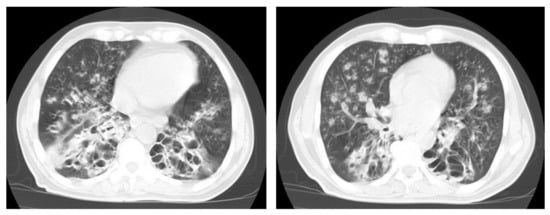

Figure 11. Post-primary-TB in a 45-year-old man. Selected axial and coronal reconstruction images of chest CT show multiple thick-walled cavitary lesions (arrows) in both lungs, with left pneumothorax as a complication of TB. Surgical emphysema in the left chest wall, due to chest-tube insertion.

Even after full treatment of pulmonary TB, complications and residual changes may affect quality of life; these complications can be misinterpreted as other active diseases, causing diagnostic pitfalls. TB complications in the lung parenchyma include tuberculoma, thin-walled cavities, cicatrisation collapse (Figure 9), and lung cancer, although this is rare. Complications in the airway include bronchiectasis (Figure 10) and tracheobronchial stenosis. Extrapulmonary complications include pleural thickening and calcification, fibrothorax, bronchopleural fistula, and pneumothorax (Figure 11). Vascular complications include Rasmussen aneurysm, calcified mediastinal lymph nodes, fibrosing mediastinitis, and constrictive pericarditis [23].